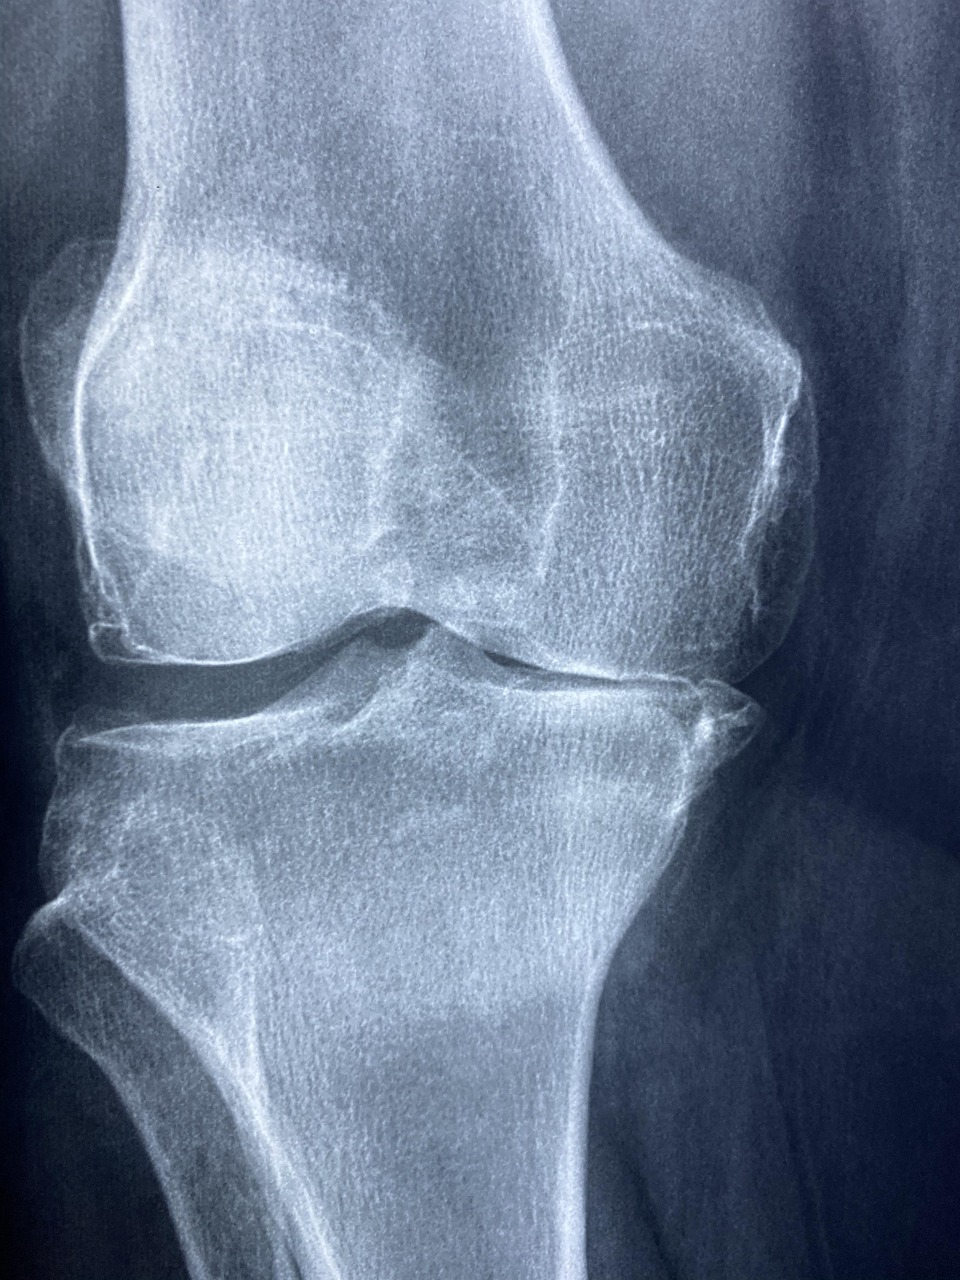

무릎 통증 정확한 진단

무릎 통증이 2주 이상 지속되거나 일상생활에 지장이 있다면 반드시 정형외과 진료를 받아야 합니다.

무릎 통증 검사

- X-ray: 뼈와 관절 간격 확인

- MRI: 연골, 인대, 반월상 연골 상태

- 초음파: 염증, 관절액 확인

- 혈액검사: 류마티스 인자 확인